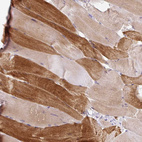

Immunohistochemical staining of human skeletal muscle shows moderate cytoplasmic positivity in myocytes.